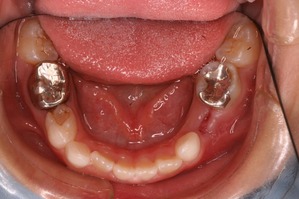

経過をみていくと、変な部分から大人の歯が生えてきました。

乳歯列時期に重篤な虫歯になった場合、あとから生えてくる永久歯は変な場所から生えてくることが多々あります。

理由は、乳歯が虫歯菌によって感染している状況下において、その上にある永久歯の卵はそのままの状況では自分も感染してしまいます。 まれに感染してしまった大人の歯は色が黒ずんだり、形がいびつな奇形的な歯になってしまいます。 多くの場合は感染した乳歯から離れていくのです。 つまり、永久歯の卵は避難しているわけです。

この状況をふりかえってみてもそうでした。

変なところから生えてきた永久歯を正常な方向に誘導するためには、その隣の乳歯も抜歯せざるを得ない状況になってしまいました。

また、一方でそうなると、反対側の乳歯の交換も促進していかなければ左右対称な歯列が完成しません。

この状況ではいくつかの乳歯をいっぺんに抜歯するといった処置をおこなう必要がありました。